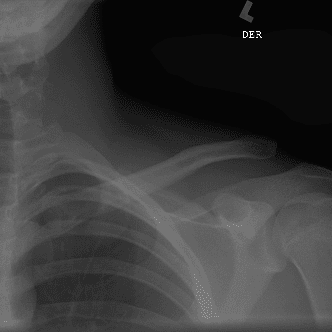

Simuliert den Dienst durch subtile oder schwierige Fälle und einige Normalbefunde.

30 Fälle